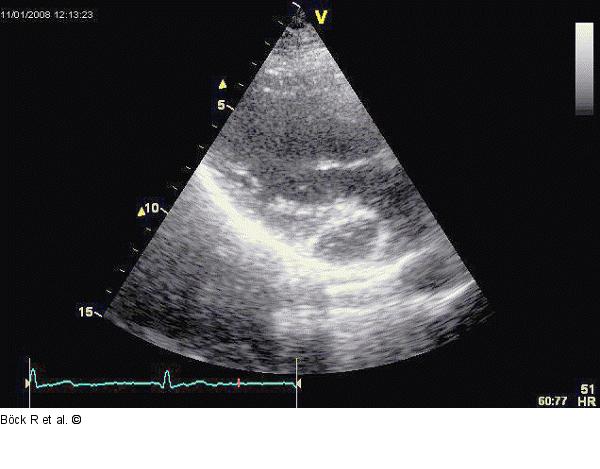

Abbildung 3: Sinus coronarius Parasternaler Längsschnitt mit Kontrasmittel im erweiterten Sinus coronarius |

Parasternaler Längsschnitt mit Kontrasmittel im erweiterten Sinus coronarius |